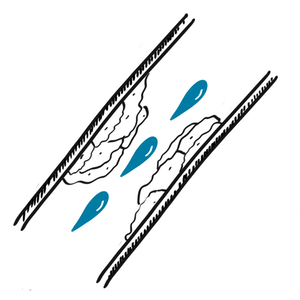

Estenosis arterial causada por placa.